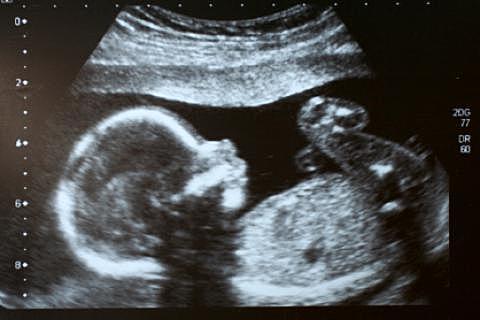

• segunda ecografia

segunda ecografia

fue realizada al 7 mes de gestación y se le es comunicado a la madre el sexo del embrión y que esta en perfectas condiciones de vida